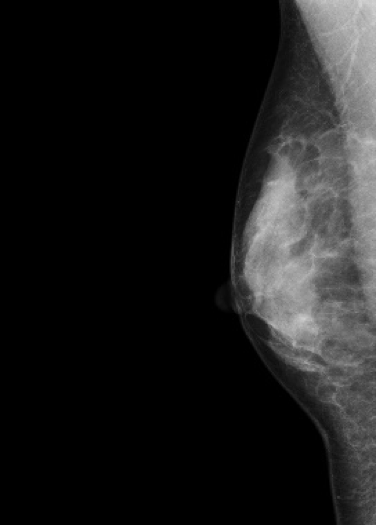

マンモグラフィ検査

装置の紹介

当院では2016年5月に乳房撮影装置

MAMMOREX Pe・ru・ru DIGITAL

(キヤノンメディカルシステムズ)を導入しました。

FPDを搭載した装置で、解像力やコントラストが向上し微細な石灰化や腫瘤をより鮮明に描出することが可能です。検査は健診棟の女性専用エリア内に併設されたマンモグラフィ専用の検査室で行っており、安心して検査を受けていただけます。撮影はNPO法人日本乳がん検診精度管理中央機構の認定を受けた女性技師が担当します。

マンモグラフィとは

専用の装置を用いて行う乳房のX線撮影のことです。 マンモグラフィは視触診では分からない早期乳癌の微細な石灰化や、触っても分からない小さなしこりの描出に優れています。

*当院では左右の乳房それぞれで2方向の撮影(CC撮影・MLO撮影)を計4枚行います。

*2方向から撮影を行うことで乳房全体をまんべんなく写すことができます。

圧迫の必要性

厚みのある乳房の中にはたくさんの乳腺や脂肪などが重なって存在しています。

これらを均等に伸ばし組織同士の重なりを分離することで、小さなしこりや石灰化の粒をより見つけやすい画像にすることができます。

*実際に乳房を圧迫する時間は1枚の撮影で数十秒程度です。

画像1枚目:圧迫なし、画像2枚目:圧迫あり